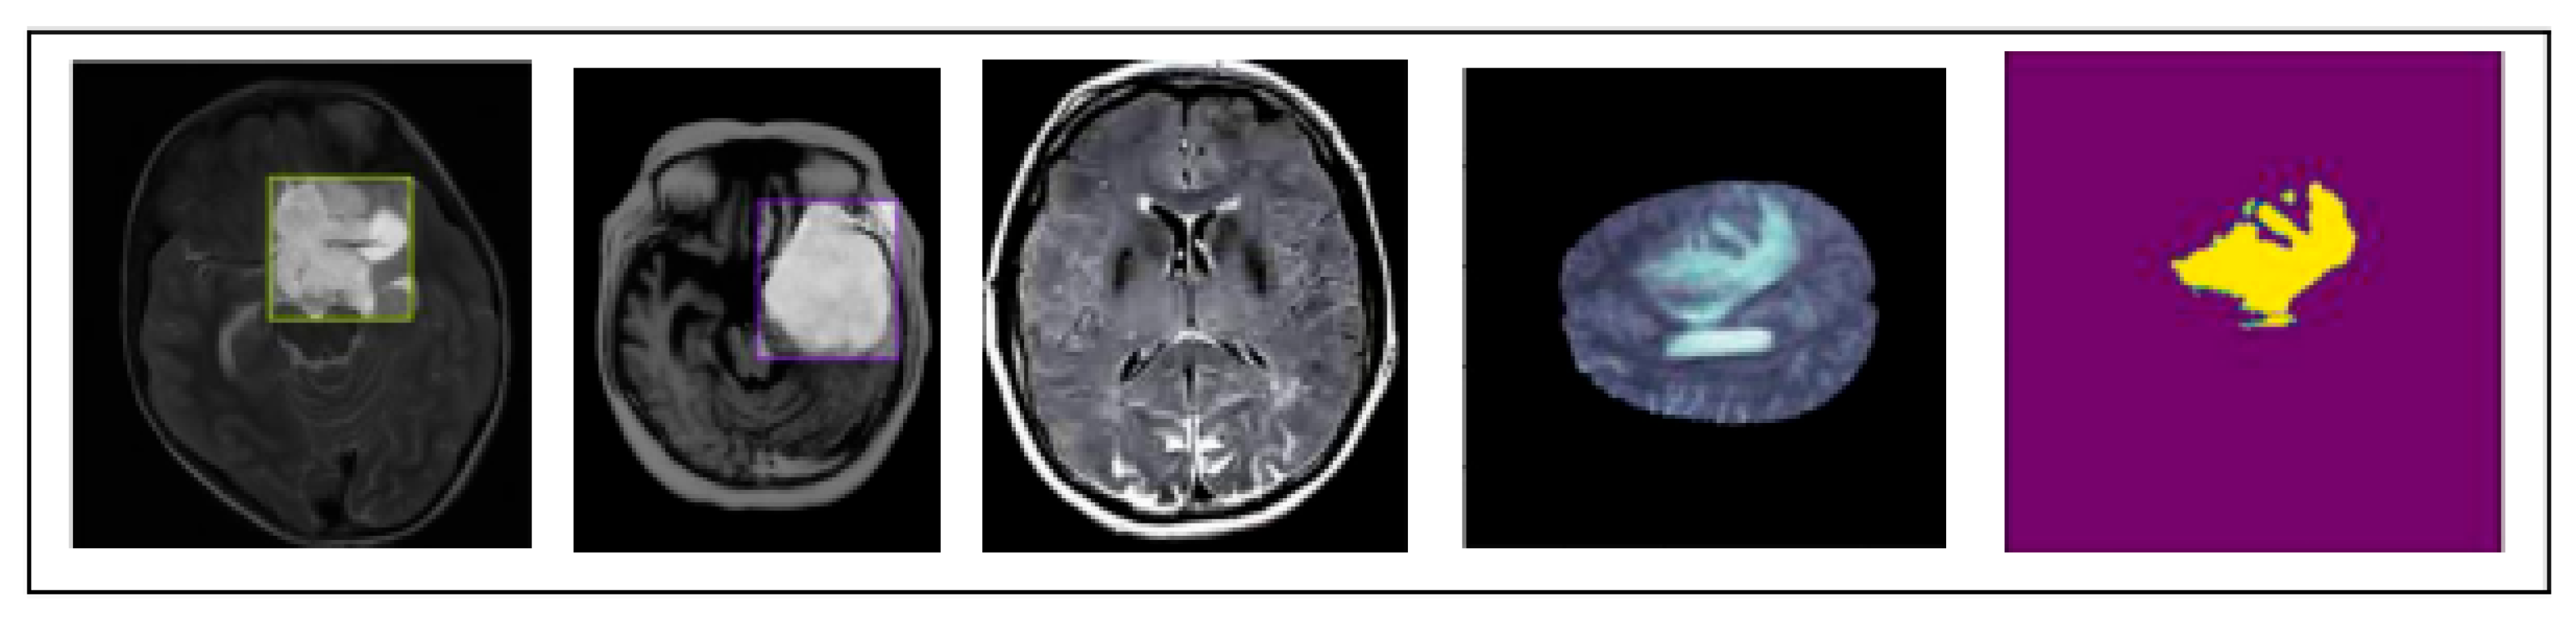

Figure 3. Visual representation of an MRI image provided in dataset.